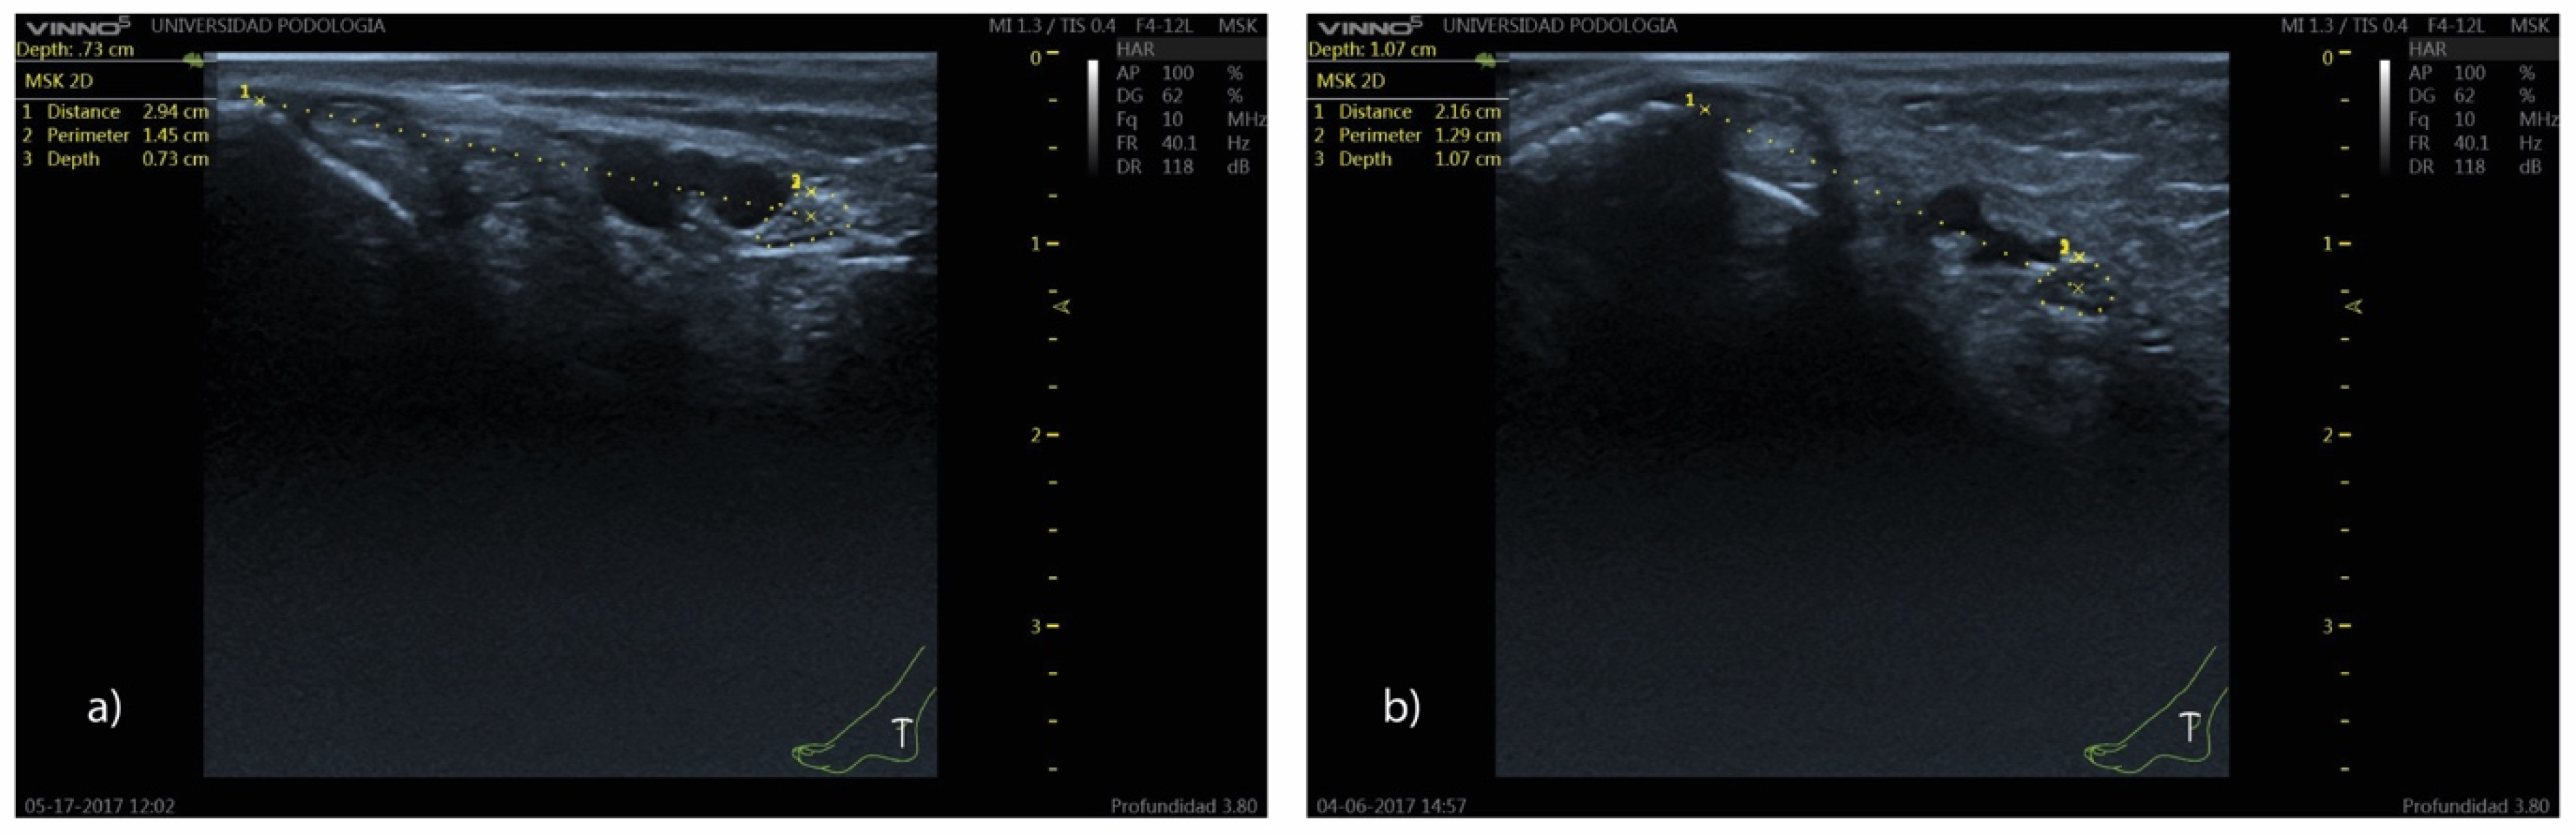

- Distance (D): from the most prominent point of the medial malleolus to the center of the TN.

- Depth (d): perpendicular distance from the skin surface to the upper edge of the tibial nerve perimeter.

- Perimeter (P): measured along the outer contour of the TN.